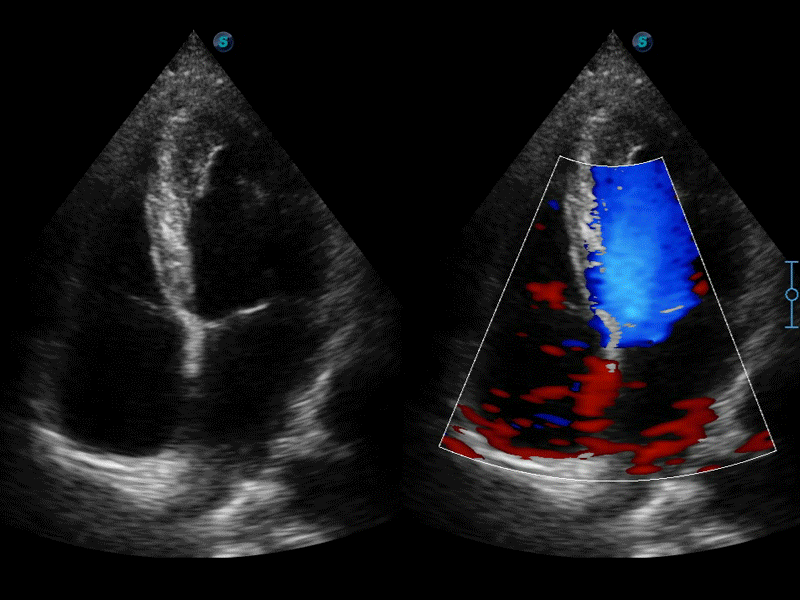

凸陣、線陣和相控陣探頭進行實時掃描時,開啟擴展成像模式,可以擴展超聲圖像視野,以便更完整地查看大的病灶或組織器官的解剖結構。

通過色彩血流和實時寬景相結合,可觀察到完整的靜脈或動脈的血流,方便醫(yī)生檢查。實時掃查過程中,如有任何操作失誤也可以很容易地進行回掃擦除,而不會中斷掃查。